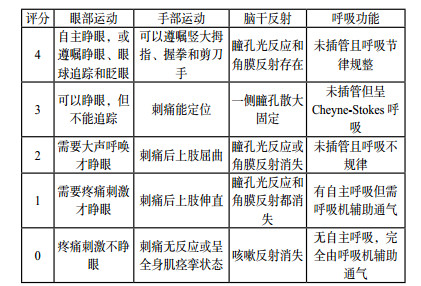

1 量表评估DOC评估最常用的方法就是评分量表,通常包括评价指标(变量)、评分标准和评分数值三个部分。通过分值计算得出分数,从而进行量化评价。评价指标的选择应遵循简易、方便、直接、常规、实用、可重复的原则。诞生于1974年的格拉斯哥评分(Glasgow Coma Scale,GCS)是评估昏迷和意识障碍患者应用最广泛的评估手段[1-4],并成为多种临床评分的重要组成部分,例如APACH Ⅱ评分、SOFA评分、WFNS评分等。但随着临床实践的不断深入和积累,GCS评分也暴露了一些缺陷,如缺乏脑干功能的评估;忽略了瞳孔变化的观察在神经重症患者诊疗中的重要意义;特殊人群(儿童、老年痴呆患者、闭锁综合症患者等)的不适用性[5-6]。因此,一些学者在GCS评分的基础上进行了修正和补充,演变出Glasgow-Pittsberg评分[7]、Adelaide儿科昏迷评分(Adelaide Pediatric Coma Scale,APCS) [8]、格拉斯哥-列日评分(Glasgow-Liège Scale,GLCS)[9]、FOUR(Full Outline of UnResponsiveness)评分(图 1)[10]、西方神经感官刺激(Western Neuro Sensory Stimulation Profile,WNSSP)[11]、因斯布鲁克昏迷量表(Innsbruck Coma Scale,ICS)[12]等。

| 图 1 全面无反应性量表评分细则 |

2005年美国Wijdicks和同事们提出的全面无反应性量表—FOUR评分,曾被誉为“新时代的格拉斯哥评分”。研究证实,相对于GCS评分,FOUR评分能提供更多的神经系统细节,更准确、更适合于神经重症患者的临床评估[13-15]。